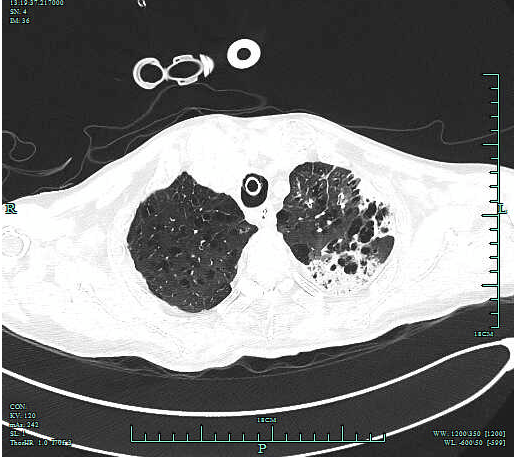

患者吴磊(化名) , 男 , 80岁 , 由于咳嗽、咳痰1周 , 加重并发热3天收住我院呼吸重症监护室 , 胸部CT提示双肺多发渗出实变 , 且患者合并呼吸衰竭 , 病因尚不明确 。 入院立即予以气管插管辅助机械通气、积极抗感染、利尿、呼吸支持等 , 症状未见明显改善 , 为患者实施胸水脱落细胞学检查提示:发现异形细胞 , 高度怀疑肿瘤 。

因患者病情危重 , 出科检查及进行有创操作的风险极高 , 为进一步明确诊断 , 医师与家属协商后在床旁 超声下行“超声定位引导下左肺穿刺活检术” 。

整个过程实时动态观察 , 操作流畅 , 医师配合默契 , 顺利获取组织 , 患者无不适反应 , 操作过程全程心电监测 。 活检标本送病理科 , 随访病理诊断:肺穿刺活检组织——浸润性腺癌(低分化) 。